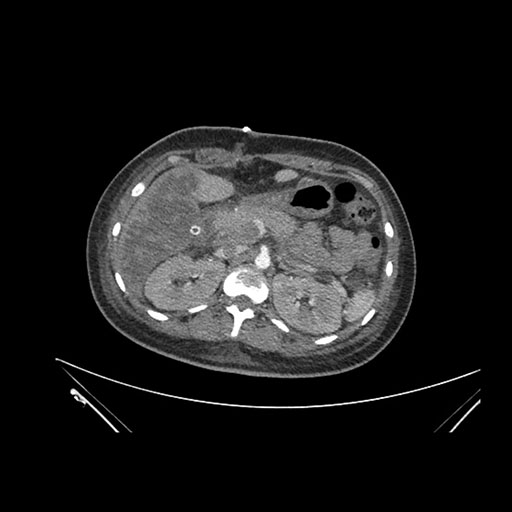

Imaging Analysis

Look through the patient's CT scan to identify any areas of concern for the necessary procedure.

Axial Venous